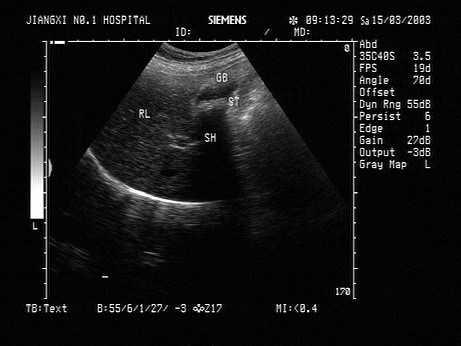

胆囊正常报告单

胆囊正常报告单,正常精子报告单

胆囊

胆囊有多大

胆囊位置

胆囊在哪个位置